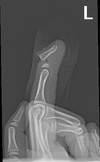

Describe this fracture?

A

BENNETT

- Oblique fracture through base of the first metacarpal, with dislocation of the radial portion @ articular surface

- produced by direct force applied to end of metacarpal; dorsal capsular structures disrupted by dislocation; marked tenderness along medial base of thumb

• thumb spica x 4 weeks